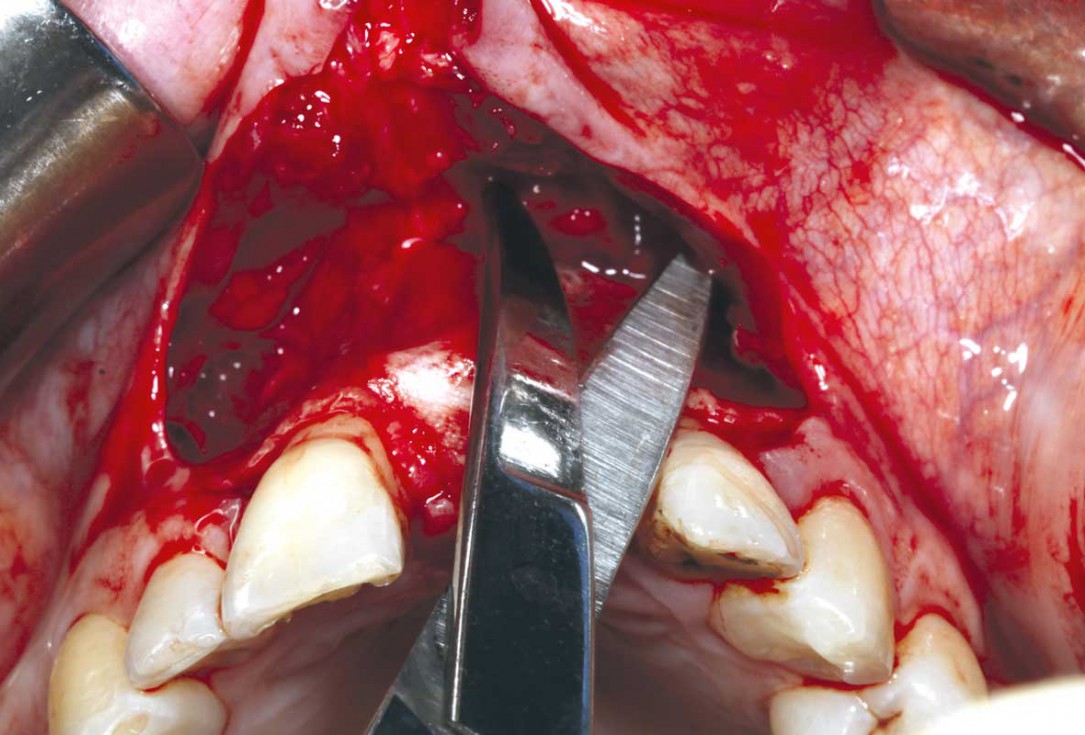

13/35 - Soft tissue adjustment - frenulum adjustment and muco-periosteal release to achieve full closure under no tension to allow the flap margins to heal with primary intensionBlock grafting in the aesthetic zone with maxgraft®, Jason® membrane and cerabone® - Dres. H. Maghaireh and V. Ivancheva

14/35 - Soft tissue adjustment - frenulum adjustment and muco-periosteal release to achieve full closure under no tension to allow the flap margins to heal with primary intensionBlock grafting in the aesthetic zone with maxgraft®, Jason® membrane and cerabone® - Dres. H. Maghaireh and V. Ivancheva